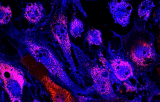

The balanced chromosomal translocation t(8;21) is found in about 90% of acute myeloid leukemia (AML) patients. AML is a heterogeneous clonal disorder of hematopoietic progenitor cells and one of the most common malignant myeloid disorders in adults. The runt related transcription factor 1 gene (RUNX1) and RUNX1 translocation partner 1 (RUNX1T1) gene are both involved in the transcriptional regulation of genes during normal hematopoiesis. The non-random translocation t(8;21) (q21.3;q22.1) is strongly associated with the French-American-British (FAB) phenotype M2 (AML-M2) and produces a chimeric gene consisting of the 5‘-region of the RUNX1 gene fused to the 3‘-region of the RUNX1T1 gene. The chimeric protein is thought to be associated with the nuclear corepressor/histone deacetylase complex to block hematopoietic differentiation. Fluorescence in situ Hybridization (FISH) can provide important information for the management of patients with hematologic disorders.